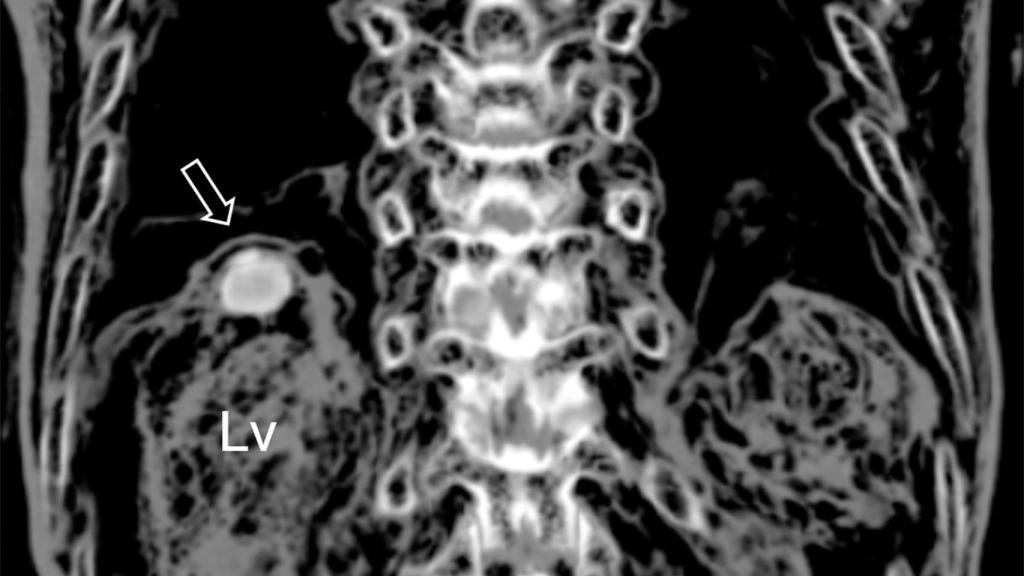

La infección detectada en el hígado de la momia.

La infección detectada en el hígado de la momia. Journal of Parasitology

El cuerpo momificado de Lee se encontraba en muy buenas condiciones cuando fue desenterrado por los arqueólogos en 2014. Con la autorización de sus descendientes, el equipo de investigadores dirigido por Min Seo de la Facultad de Medicina de la Universidad Dankook de Corea del Sur escaneó la momia, detectando una extraña protuberancia en su hígado.

Tras analizar dicha tumoración, los investigadores encontraron huevos de color marrón-dorado, de aproximadamente 85 micrómetros de largo, los cuales se habrían producido por una infección por Paragonimus westermani. En otras palabras, esto significaría que Jing Lee sufrió paragonimiasis hepática cuando murió, convirtiéndose en el caso más antiguo conocido de esta dolencia.